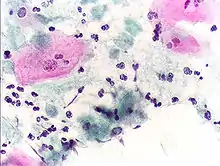

Endocervical adenocarcinoma on a pap test.

Endocervical adenocarcinoma on a pap test. Candida organisms on a pap test.